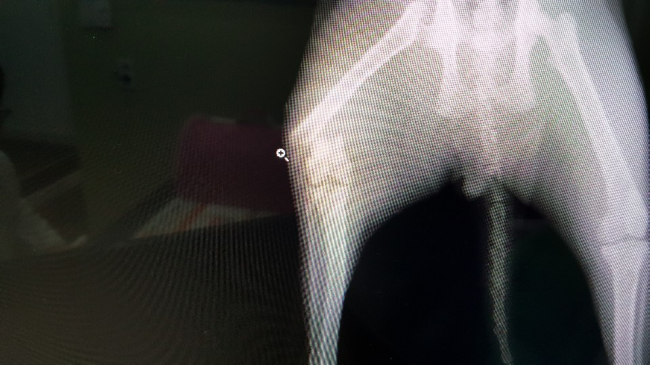

치료중 대상묘

치료완료후